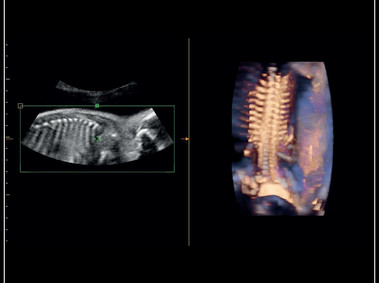

Giải pháp siêu âm sản phụ khoa toàn diện với chế độ 3D/4D và công nghệ X-light – bố trí nguồn sáng và làm mịn da mặt em bé